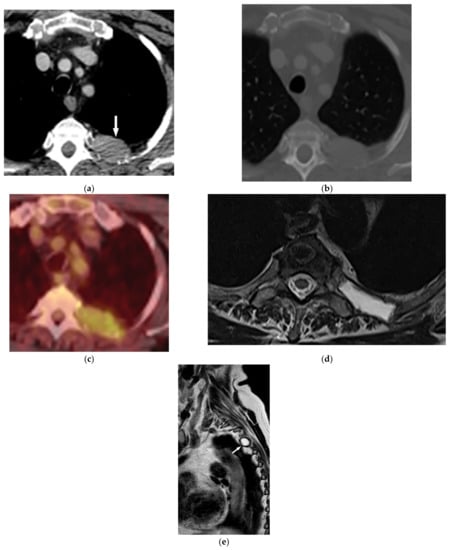

11.3. Mesothelioma

Malignant mesothelioma is the most common primary tumor of the pleura, which is related to prior asbestos exposure with a relatively poor prognosis [56].

Multidetector CT effectively reveals the primary tumoral extension, lymphadenopathy, and extrathoracic metastasis (Figure 27 and Figure 28) [56]. Another CT finding is circumferential pleural thickening (most common finding) with extension along the fissures. Large or punctate osseous or cartilaginous differentiation is more in favor of malignant mesothelioma rather than linear calcification that usually occurs within asbestosis plaques. Dynamic contrast-enhanced computed tomography (DCE CT) enables measuring intratumoral capillary permeability and blood flow, which are beneficial in evaluating treatment response [56,57,58].

Figure 27.

A 67-year-old man with dyspnea and chest pain. Contrast-enhanced CT in axial (a) and coronal (b) planes demonstrate left-sided localized enhancing pleural mass (arrow) with internal areas of necrosis that extend to the posteromedial aspect of the chest wall. Involvement of diaphragmatic pleura and elevation of left hemidiaphragm are also identified.

Figure 28.

A 70-year-old man with dyspnea. The non-contrast CT in the axial plane demonstrates right-sided large pleural effusion, near complete collapse of the right lung (a) after the chest tube insertion; thick circumferential nodular pleural thickening of parietal pleura was shown (arrow) (b). Contrast-enhanced CT of the upper abdomen shows the extension of mesothelioma through the abdominal cavity and wall with indentation over adjacent liver parenchyma (arrow) (c).

MR imaging and 18F-FDG PET/CT are useful in further evaluation of chest wall, diaphragm, and mediastinal invasion [56,57,58,59]. Malignant mesothelioma appears as unilateral hyperintense pleural effusion and pleural thickening with iso to slight hyperintensity to chest wall muscles on T1-weighted and moderate hyperintensity on T2-weighted images. Post-contrast enhancement is expected (Table 3). It is believed that higher metabolic activity on 18F-FDG PET/CT is associated with poor prognosis and shorter survival time [25,56,57,58].